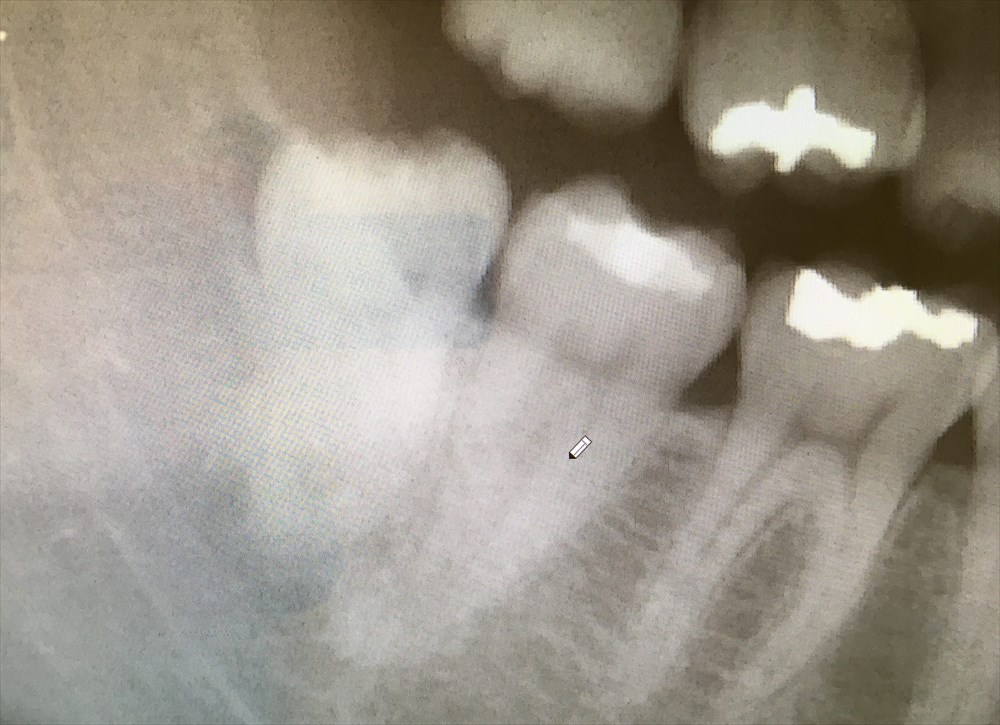

このように、2次元のレントゲンでは分かりにくい根の形も、CTなら事前に確認できます。